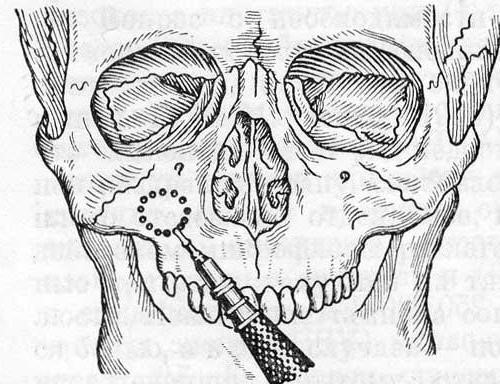

При образовании патологических очагов (полипов) требуется операция на гайморовой пазухе – гайморотомия. Объем хирургического вмешательства определяется размерами патологически разросшихся тканей в пазухе: при ограниченном процессе проводят щадящую гайморотомию, при значительном поражении пазухи – радикальную операцию (по Колдуэллу-Люку).